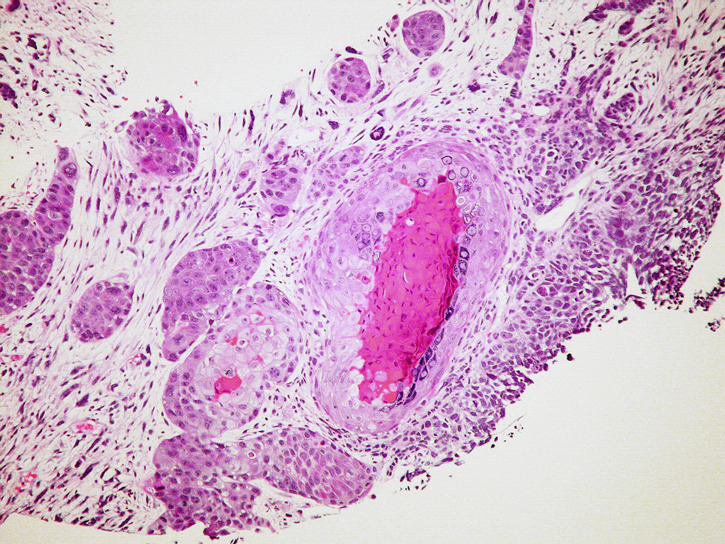

In a recent report, researchers at Johns Hopkins Kimmel Cancer Center have released their new studies on cancer - which they are doing with the help of evolutionary game theory! Their goal is to figure out how cells collaborate within a tumor and make energy, and with that, identify the best time to disturb the metastatic cancerous process.

Tumor cells have various cooperative and competitive states which vary as the tumor grows. Applying game theory to this process, the scientists found that there are a series of critical periods, based on mutation rates in which the cells in the tumor change their game-like strategy.

Some tumor cells may stimulate surrounding normal cells to release lactate which, in turn, feeds the tumor. A therapy that disrupts this system, while it is in a critical transition, could help to shut down the tumor and pave the way for anti-cancer therapies to take effect.

- Photo: by Yale Rosen. Cancerous Cell.